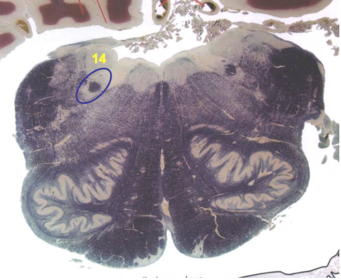

| Superior cerebellar peduncle | |

| Dentate nucleus | |

| Fastigial nucleus | |

| Anterior spinocerebellar tract | |

| Spinal nucleus of V | |

| Spinal tract of V | |

| Middle cerebellar peduncle | |

| Superior vestibular nucleus | |

| Medial lemniscus | |

| Trapezoid body | |

| Ventral trigeminothalamic tract | |

| Superior olive | |

| Longitudinal pontine fibers (corticospinal tract) | |

| Transverse pontine fibers (dark fibers) | |

| Pontine nuclei (pale) | |

| Central tegmental tract | |

| ALS | |

| Medial longitudinal fasciculus | |